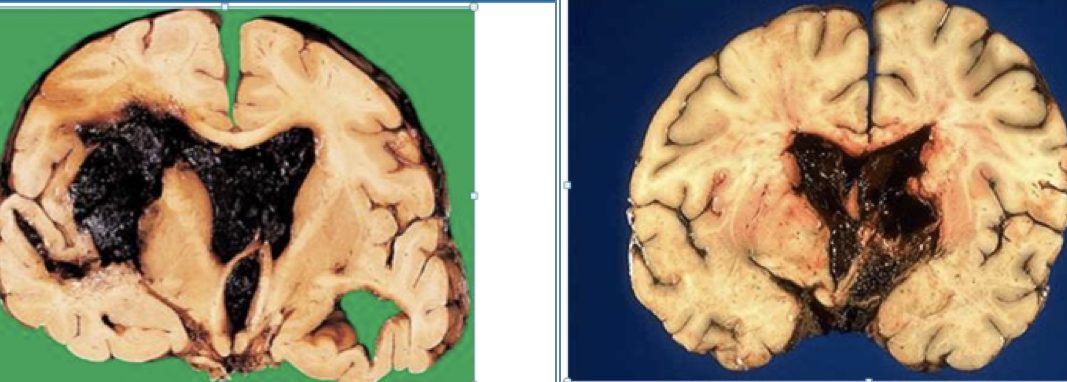

Morphology

• Slit haemorrhages: Microbleeds that scar

• Lacunar infarcts: Pale, cavity-like lesions in brainstem

Hypertensive stroke, Lacunar infarct